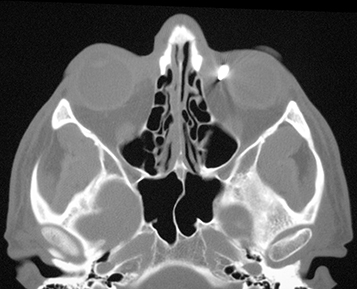

Figure 3.22.2: Computed tomography (CT) of intraorbital foreign body.